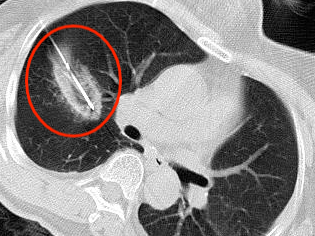

近年来,贵州航天医院各科室紧跟医学前沿,不断强技术、补短板,大力开展新技术、新项目,完成了许多高精尖、高难度、本地区“首例”的技术,填补了医院医疗技术空白,满足了群众日益增长的医疗需求。 贵州航天医院呼吸与危重症医学科是贵州省内呼吸疾病治疗规模最大,诊疗项目最全的呼吸疾病品牌科室,呼吸介入技术达到了全国先进水平,在贵州省内处于领先的地位。 本期,我们将为大家带来呼吸与危重症医学科特色技术——氩氦刀冷冻消融技术治疗肺癌、高危肺结节。 案例分享 患者在体检时发现右肺结节(10mm),就诊于当地我院一专科联盟合作医院,但因当地医疗条件有限,患者通过专科联盟绿色通道前往我院就诊,入院后,通过经皮肺穿刺活检,病理诊断为右肺原位腺癌,科室立即组织专家开展肺结节多学科会诊(MDT),为患者制定诊疗方案。 经充分的沟通下,患者及家属拒绝手术切除。科室再次严格讨论评估,患者情况满足氩氦刀冷冻消融术指征,再次将治疗方案与患者及家属沟通同意后,为患者制定并成功实施氩氦刀冷冻消融术。 冷冻消融术中 术后,患者定期复查,恢复效果良好。 术前 术后即刻 术后1月(反应性增大) 术后6月(纤维条索) 术后12月(纤维条索变细) 什么是氩氦刀冷冻消融技术 氩氦刀冷冻消融技术是一种先进的微创超低温冷冻消融肿瘤的医疗技术,它利用氩气和氦气的快速温度变化特性,实现对病变组织的精准冷冻和复温,以达到消融和破坏肿瘤细胞的目的。 氩氦刀冷冻消融技术原理 氩氦刀冷冻消融技术基于焦耳-汤姆逊效应,通过氩气和氦气的快速交换实现局部组织的超低温冷冻(-140℃到-190℃)和快速复温(20℃到45℃),当氩气通过金属杆尖端的蒸发器时,其气压突然降低,会大量吸收周围的热量,使金属杆尖部的气温迅速下降到超低温;随后,氦气在极短的时间内使组织迅速复温,通过热胀冷缩的原理,使肿瘤细胞爆裂。 (一)直接杀伤( 靶区冷冻消融效应) 1.快速冷冻(降温段):细胞内冰晶快速生长并撕裂细胞,导致细胞损坏。 2.慢速冷冻(低温段):细胞外冰晶生长导致水渗出细胞,造成细胞脱水。 3.升温:水迅速进入细胞,导致细胞涨破。 (二)间接杀伤( 冷冻的血管栓塞效应) 病灶区域快速冷热交替,引起微血管细胞脱水、蛋白质变性、微血管损伤、 冰晶及微血栓在微血管内形成,导致血小板聚集、血管栓塞, 局部细胞缺血坏死。 (三)抗肿瘤免疫( 冷冻免疫激活效应) 随着肿瘤细胞的破裂和坏死,促使肿瘤免疫调节因子停止分泌,逆转免疫抑制状态;可调控表面抗原,促进淋巴细胞增殖,提高身体抗肿瘤免疫能力。 氩氦刀冷冻消融技术优势 (一)精准度高:通过精确的靶点定位和温控技术,可实现对病变组织的精准冷冻和复温,避免损伤正常组织。 (二)微创治疗:对周围正常组织的热损伤小,无需开胸开腹,仅有一个针孔,恢复快,几乎无疤痕。 (三)适应症广:肺腺体前驱病变(癌前病变)、甲状腺结节、乳腺结节等;多原发磨玻璃肺结节,因各种原因不适合手术的早期肺癌、肝癌等;内科治疗无法控制的少发转移瘤等。 (四)可重复治疗:由于冷冻治疗对身体的创伤和痛苦较小,可以多次重复进行治疗,这对巨大的肿瘤和多发的肿瘤尤其适用。 (五)无毒性:冷冻治疗是以物理方法杀灭肿瘤,不向体内注射任何药物,避免外科手术、化放疗等对身体带来的巨大创伤和毒副作用,能有效减轻患者肿瘤负荷和痛苦,因此与化放疗、分子靶向药物等治疗方式相比属于无毒治疗。 氩氦刀冷冻消融技术对于早期肺癌、高危结节,可作为手术的替代治疗。对于晚期较大的肿瘤可作为姑息治疗,增强综合治疗的效果,可减少肿瘤负荷,减轻症状,提高生活质量,延长生存时间。 近年来,随着医学影像技术发展和肺癌筛查的广泛开展,肺内结节的检出率显著提高。无论肺内磨玻璃结节还是实性结节,单发或多发,都需要引起重视,定期复查,动态观察结节变化,如有需要请积极治疗。 贵州航天医院 呼吸与危重症医学科专家团队 廖江荣 国务院政府特殊津贴专家、遵义市呼吸疾病临床医学中心学科带头人、二级教授、主任医师 学术任职: 亚洲冷冻治疗学会副主席 第二届中国医药教育协会介入微创专业委员会呼吸分会副主任委员 中国抗癌协会肿瘤微创治疗专业委员会常务委员 中国防痨协会结核病转化医学专业分会常务委员 第一届中国人体健康科技促进会呼吸介入专委会常务委员 中国医疗保健国际交流促进会结核病学分会第三届委员会常务委员 中国抗癌协会肿瘤微创治疗专业委员会粒子治疗学组第四届委员会委员 中国结核病防治综合质量控制专家指导委员会委员 “西部呼吸介入联盟”副理事长 专业擅长: 呼吸系统(肺)疑难病的诊断及危重病的抢救,呼吸系统(肺)感染性、疑难性疾病介入快速诊断(ROSE),尤其在肺癌、肺小结节早期诊断,肺癌微创综合靶向治疗,难治性、复治性、重症肺结核诊疗,硬质支气管下复杂性气道狭窄诊治,纤支镜介入治疗气道肿瘤、结核、气道狭窄(球囊扩张、支架植入、高频电刀、氩气刀、冷冻、灌洗、注药、微波消融),间质性肺疾病的诊疗上具有极高水平;带领团队勇于创新,在贵州省率先开展多项新技术、新疗法,如CT引导下及纤支镜下I125粒子植入及CT引导下微波、冷冻消融介入治疗肺癌等多项新技术,带动了贵州省肺部疾病的介入治疗水平提高。 唐永江 四川大学华西医院 呼吸与危重症医学科 副主任医师 呼吸危重症医疗组长 香港中文大学博士 美国康奈尔大学访问学者 贵州航天医院 呼吸与危重症医学科 学科带头人 主要从事呼吸危重症(特别是呼吸重症感染)的临床及科研工作。 PCCM专培结业医师 中华医学会呼吸病学分会呼吸危重症学组秘书 中华医学会呼吸病学分会ECMO工作组成员 四川省医学会呼吸病学专委会介入学组委员兼秘书 发表文章20余篇,主持及参与多项国家自然科学基金及省卫健委基金。 蒋 婷 呼吸、感染党支部书记,呼吸与危重症医学科主任,副主任医师 专业擅长:从医20余年,在呼吸系统疾病、介入呼吸病学、肺部结核、肺部肿瘤等方面具有丰富的临床经验和专业技能,尤其是慢性阻塞性肺疾病、支气管扩张、肺结核、耐药肺结核、肺癌、胸腔积液等肺部疾病的诊治、微创介入、危重病患者抢救。 现任中国防痨协会人兽共患结核病专业分会委员,中国女医师协会第一届介入专业委员会委员,贵州省基层呼吸疾病防治联盟-间质性肺疾病联盟委员,贵州省防痨协会第七届理事会理事,贵州省中西医结合学会呼吸专业委员介入呼吸病学组委员,贵州省遵义市中医药学会中西医结合肺病(呼吸)分会副主任委员,贵州省遵义市中医药学会中医肿瘤专业委员会常委;发表论文数篇,参与并主持多项科研项目。 王 云 中共党员,呼吸与危重症医学科一病区副主任,副主任医师 专业擅长:擅长呼吸系统常见病及疑难危重症、介入呼吸病学、肺部肿瘤疾病的诊治,尤其擅长快速现场评价(ROSE)技术。 贵州省中西医结合学会呼吸专业委员会介入呼吸病学组委员,遵义市中医药学会中西医结合肺病(呼吸)分会委员,贵州省中西医结合学会第六届呼吸专业委员会委员。 李桂凤 中共党员,呼吸与危重症医学科三病区主任,副主任医师 专业擅长:从事呼吸系统疾病、结核病学、介入呼吸病学、肿瘤综合治疗、呼吸康复等临床工作20余年,擅长呼吸内科常见病、多发病及疑难重症危重病症的诊治,尤其对重症疑难结核及耐药结核病、介入治疗(肺)呼吸系统疾病、呼吸危重病抢救等方面具有较高诊疗水平。 中国防痨协会非结核病专业委员会委员,贵州省中西医结合学会第六届呼吸专业委员会委员,贵州省康复学会睡眠障碍康复专业委员会委员,遵义市呼吸内科医疗质量控制中心委员,遵义市落实民生实事结核病筛查阅片专家组成员;主持及参与实用新型专利3项。 周裕祥 中共党员,呼吸与危重症医学科四病区主任,副主任医师 专业擅长:经皮肺介入、经血管介入诊疗技术。 贵州省中西医结合学会呼吸专业委员会介入呼吸病学组常务委员,中国医师协会呼吸医师分会介入呼吸病学工作委员会呼吸病血管介入学组委员,贵州省中西医结合学会呼吸学分会委员,遵义市医学会放射肿瘤治疗学分会委员,中国医药教育协会介入微创呼吸分会委员,北京健康促进会中青年专家委员会胸部疾病精准活检分委会委员;曾赴重庆医科大学RICU、珠海市人民医院介入科进修学习。 杨 芳 中共党员,呼吸与危重症医学科内镜中心主任,副主任医师 专业擅长:从事临床工作约20年,对呼吸危重病的救治有独到的见解,尤其擅长呼吸系统疾病的介入诊疗,对呼吸内镜下的诊治及经皮肺穿刺诊疗技术具有丰富的临床经验。 亚洲冷冻治疗学会委员,中国医药教育协会介入微创呼吸分会委员,西南结核病医院联盟第二届委员会秘书/委员,贵州省中西医结合学会第六届呼吸科专业委员会委员,贵州省中西医结合学会呼吸专业委员会介入呼吸病学组秘书,贵州省中西医结合学会呼吸专业委员会基层康复学组副组长,贵州水利电力医学科学技术会高原医学分会委员,遵义市中医院学会中西医结合肺病(呼吸)分会秘书/常务委员,遵义市医学会肿瘤学分会(第二届)委员,遵义市医学会放射肿瘤治疗学分会第二届委员;主持及参与科研课题多项,参编著作《呼吸内镜操作技术规范》、《介入结核病学》,发表论文数篇。 贵州航天医院 呼吸与危重症医学科简介 贵州航天医院呼吸与危重症医学科以呼吸危重症和介入呼吸病学为强力推手,以肺部感染性疾病及肺癌、肺小结节的早期精准诊疗、慢性呼吸疾病康复治疗为特色,以人才团队建设为核心的科室发展模式,现已成为贵州省内呼吸疾病治疗规模最大、诊疗项目最全的呼吸疾病品牌科室。是贵州省医学重点学科、临床医学重点专科建设单位,遵义市首批呼吸重点学科、重点专科建设单位。是国家卫健委能力建设和继续教育肿瘤微创介入建设中心、贵州省县级医院微创介入培训中心、遵义市呼吸疾病临床医学中心。是国家呼吸医疗质量控制与管理哨点医院、遵义市呼吸内科专业医疗质量控制中心。是中国医药教育协会介入微创呼吸分会呼吸介入技术培训中心单位;国家卫健委海医会呼吸分会ROSE专委会“诊断性介入肺脏病学快速现场评价”培训基地;中国肺癌防治联盟“贵州航天医院肺结节诊治”分中心,中国人体健康科技促进会呼吸介入技术培训基地,贵州省中西医结合会呼吸学分会呼吸介入专委会主委单位。 基本情况 平均每年开展气管镜诊疗约4000例,经皮肺穿刺介入诊疗近千例,开展的项目包括经支气管镜(软、硬)下冷冻、氩气刀、高频电刀、球囊扩张、支架置入、超声内镜诊疗等气道介入诊疗技术,经皮肺穿刺活检及肿瘤消融术(微波、冷冻)、ROSE技术、内科胸腔镜诊疗及经血管介入诊疗技术,且多项呼吸介入诊疗技术在省内处于领先水平。 诊疗范围 专科擅长:致力于呼吸系统感染性、疑难性疾病的介入快速精准诊疗;肺癌与肺小结节早期精准诊疗水平项目提升。擅长呼吸系统(肺)疑难病的诊断及危重病的救治,尤其是肺癌、肺小结节的早期诊断,肺癌综合靶向治疗,肺结核综合诊疗等肺部疾病的介入诊疗在贵州省内处于前沿水平。 肺结节MDT门诊 贵州航天医院呼吸与危重症医学科微创介入诊疗技术已达到国内前列,省内领先水平,是亚洲冷冻治疗学会常务理事单位,并获批成立遵义市肺结节多学科(MDT)微创诊疗中心。 出诊信息 出诊时间: 周一至周五 8:00--12:00;14:00--17:00 出诊地点: 遵义市肺结节多学科微创诊疗中心(MDT)门诊(贵州航天医院呼吸综合楼1楼) 呼吸与危重症医学科与心胸外科、医学影像科、麻醉科等科室建立了多学科(MDT)会诊机制,结合患者情况,通过采取外科手术、冷、热消融等多种治疗手段,帮助患者安全、有效、精准、科学、快速治疗肺结节,单次消融手术时间约半小时左右,几乎没有疼痛,且并发症少,3-5天即可出院,有效减少了患者因开刀手术需长时间恢复的痛苦。 一审一校:周裕祥、黄成成